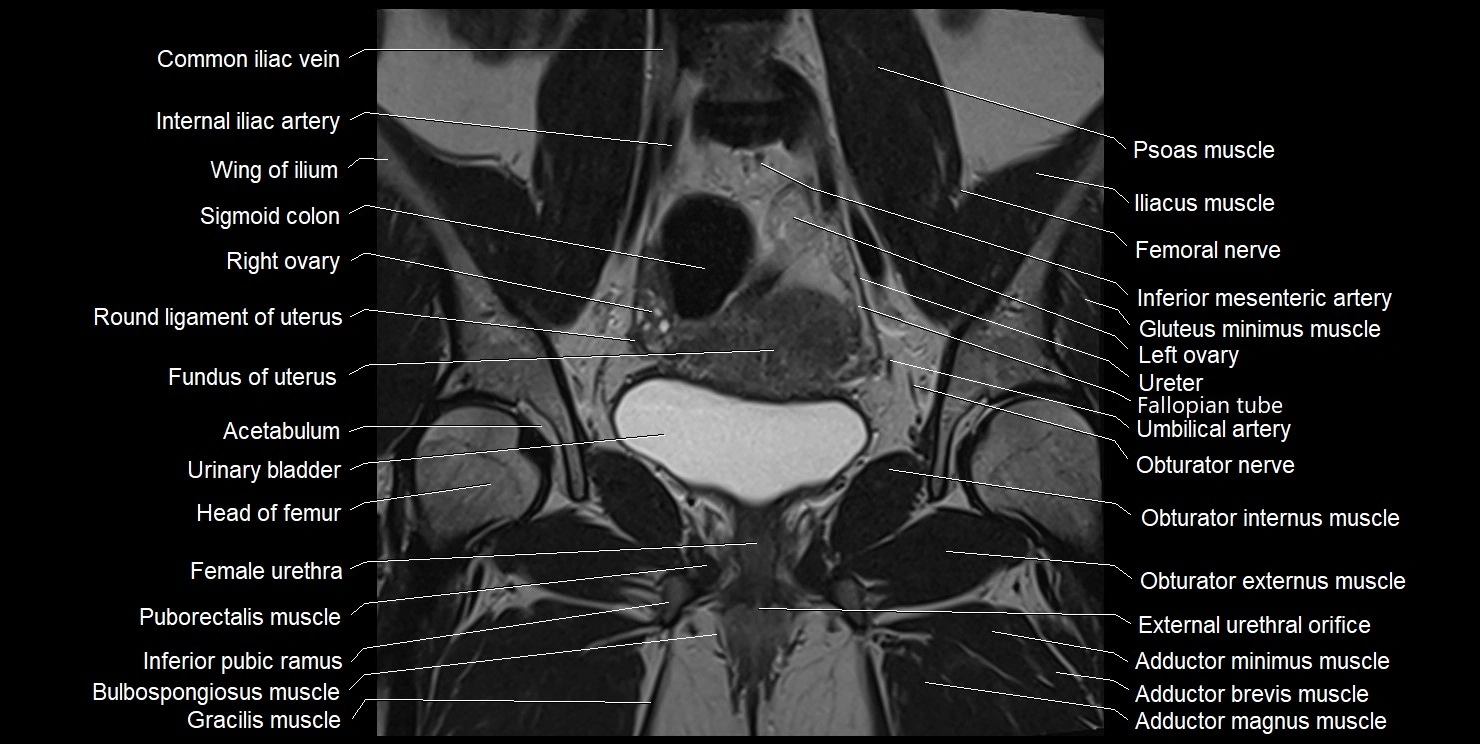

- Acetabulum

- Common iliac vein

- Fallopian tube

- Female urethra

- Femoral nerve

- Fundus of uterus

- Gluteus minimus muscle

- Head of femur

- Iliopsoas muscle

- Iliopsoas tendon

- Inferior mesenteric artery (IMA)

- Inferior pubic ramus

- Internal iliac artery

- Left ovary

- Obturator externus muscle

- Obturator internus muscle

- Obturator nerve

- Pectineus muscle

- Puborectalis muscle

- Right ovary

- Round ligament of uterus

- Superior pubic ramus

- Umbilical artery

- Urinary bladder

- Vagina

- External urethral orifice